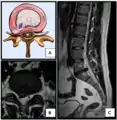

Nucleus herniating through tear in annulus (with MRI)[7]

- Magnetic resonance imaging (MRI) without contrast is a diagnostic test that produces three-dimensional images of body structures using powerful magnets and computer technology. It can show the spinal cord, nerve roots, and surrounding areas, as well as enlargement, degeneration, and tumors. It shows soft tissues better than CAT scans. An MRI performed with a high magnetic field strength usually provides the most conclusive evidence for diagnosis of a disc herniation. T2-weighted images allow for clear visualization of protruded disc material in the spinal canal.

MRI scan of large herniation (on the right) of the disc between L4 and L5 vertebrae

A rather severe herniation of the L4–L5 disc

Example of a herniated disc at L5–S1 in the lumbar spine